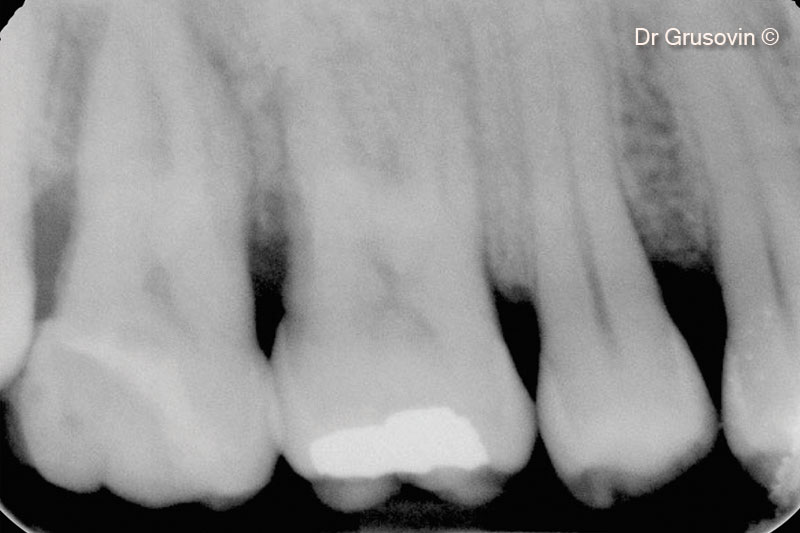

Ảnh chụp X-quang #46

Ảnh chụp X-quang trước và sau 7 năm theo dõi.